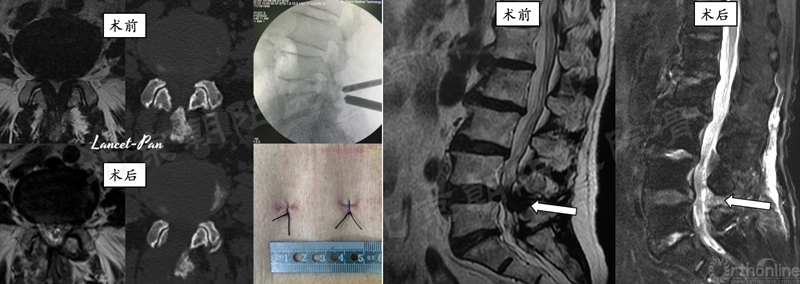

六、 典型病例分享

#10例UBE, L4/5 LSS。

#12例UBE,PLIF术后8年L3/4 ASD。

#9例UBE,ADS合并L4/5LDH。